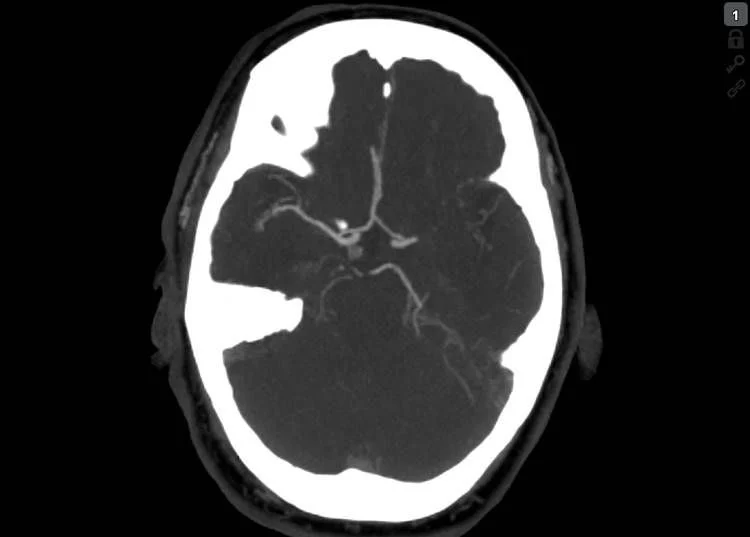

Stroke CT workup showed 16 ml well delignated infarct of the head of caudatenucleus and putamen (ASPECTS 8), a proximal left M1 occlusion and 40 ml of perfusion lesion in the MCA territory (18:25, Brainomix). No thrombolysis.

Thrombectomy was done with Embovac and Tigertriever (Rapid Medical) in general anaesthesia (door-to-groin 109 min, 19:44) with first pass recanalization TICI 2c in 16 min (20:00, door-to-final-TICI 123 min).